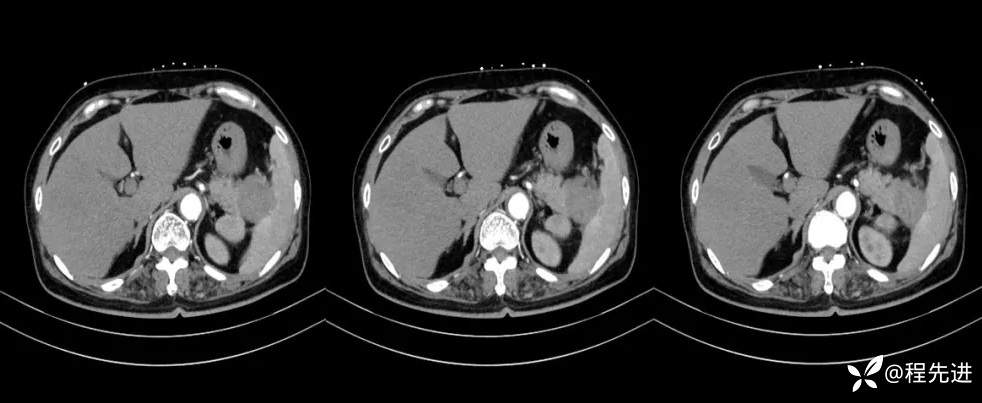

【现病史及既往史】:体检发现胰尾部肿块4年,当时手术病理提示异常增生性病变,现发现右侧顶部包块,逐渐增大,无明显感觉不适

影像检查: